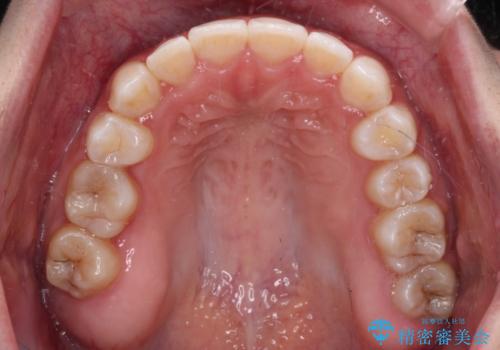

八重歯を改善 目立たないワイヤー装置での矯正治療

- 矯正装置

- 審美装置

- 八重歯を気にして来院された患者様です。

本来であれば八重歯の隣後方の歯を抜歯するのですが、その後ろの歯が乳歯であり後続永久歯もなかったため、乳歯を抜去することとしました。

前から5番目の乳歯は、後続永久歯である小臼歯と比べて幅径が大きいため、移動に時間がかかりましたが、きれいに仕上げることができました。